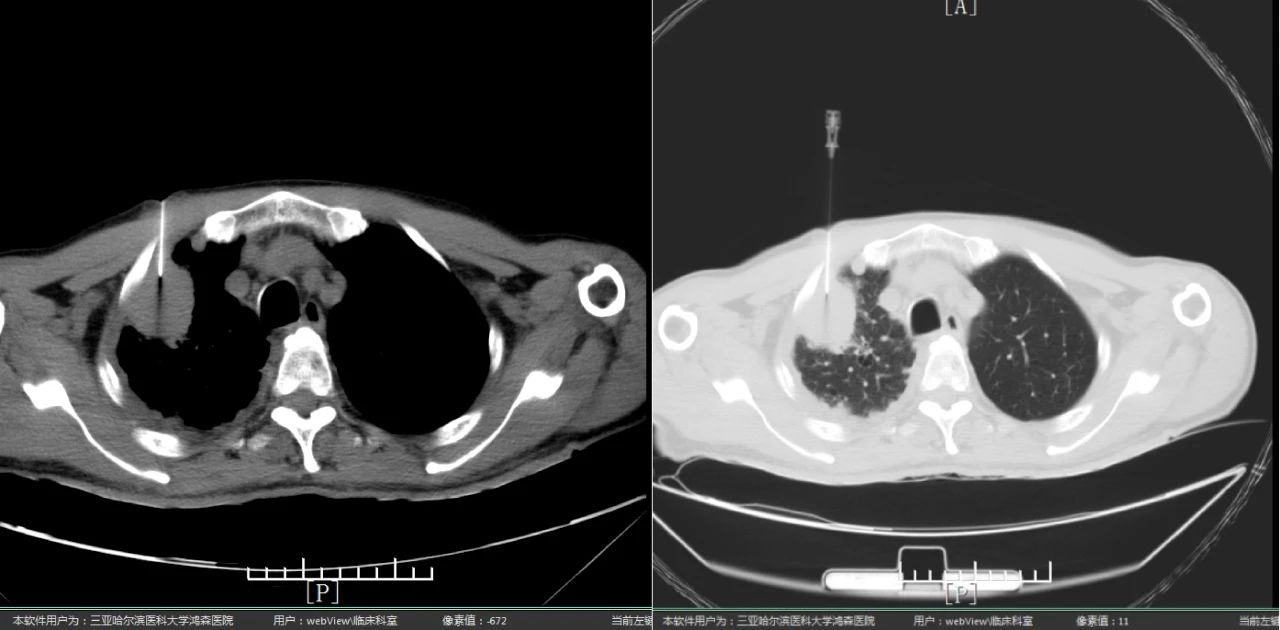

为明确肿块性质,更好地制定下一步治疗计划,经肿瘤科李玉成主任与放射影像中心王强主任研究讨论,决定行CT引导下精准定位肺部穿刺活检术。患者与家属极度焦虑与恐惧,在李玉成主任与患者及家属反复、耐心讲解此类病症的诊治及相关知识,通过沟通、安抚其情绪,取得患者及家属同意后,于5月30日在CT引导下行肺占位穿刺活检。 ▲在CT引导下行肺占位穿刺活检术 放射影像中心王强主任与肿瘤科李玉成主任共同制定了全面的操作方案,在技术组技师密切配合下,确定肺肿瘤穿刺定位,李玉成主任按照技术操作规范顺利完成穿刺活检。术后病理提示肺腺癌,基因检测为EGFR及ALK等驱动基因阴性结果。 ▲患者治疗前与治疗4周期后对比